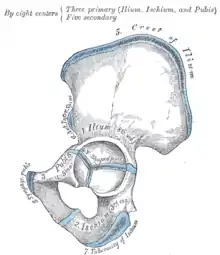

Pelvic girdle.

Overview of Ilium as largest bone of the pelvis

The crest of the ilium (or iliac crest) is the superior border of the wing of ilium and the superiolateral margin of the greater pelvis.

Structure

The iliac crest stretches posteriorly from the anterior superior iliac spine (ASIS) to the posterior superior iliac spine (PSIS). Behind the ASIS, it divides into an outer and inner lip separated by the intermediate zone. The outer lip bulges laterally into the iliac tubercle.[1] Palpable in its entire length, the crest is convex superiorly but is sinuously curved, being concave inward in front, concave outward behind.[2]

It is thinner at the center than at the extremities.